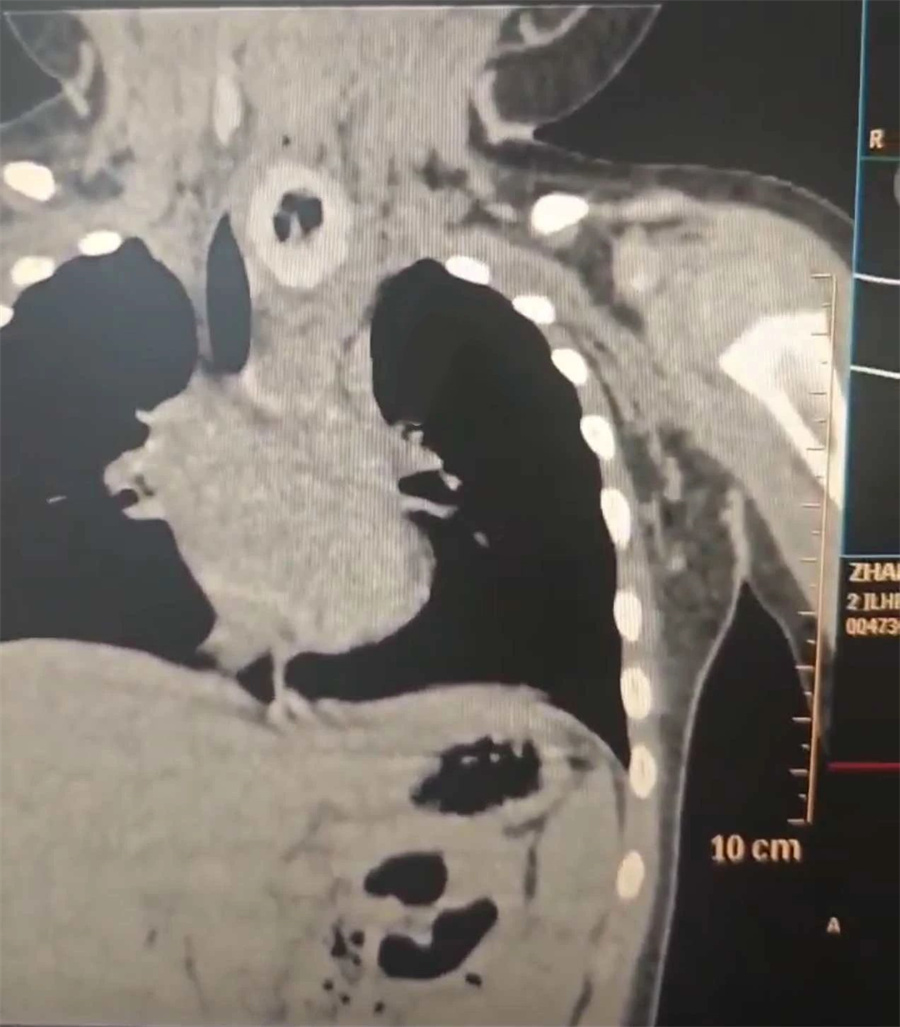

术中,杨小健副院长将食管镜沿患儿咽后壁置入,很快在距门齿约11cm处食道入口下方,发现一个较大的黄色不规则异物。异物周围黏膜已出现充血肿胀。

困扰牛牛呕吐、呛咳的“元凶”终于被消除了。随后,杨小健副院长再次置镜,在Hopkins镜引导下仔细查看,发现异物嵌顿处有黏膜溃疡破损,所幸无肉芽增生、明显穿孔及出血情况。整个手术过程非常顺利,仅用时10分钟。考虑到异物带来的后续缓慢性损伤,术后,团队对牛牛采取禁食水、抗感染及补液等对症支持治疗。